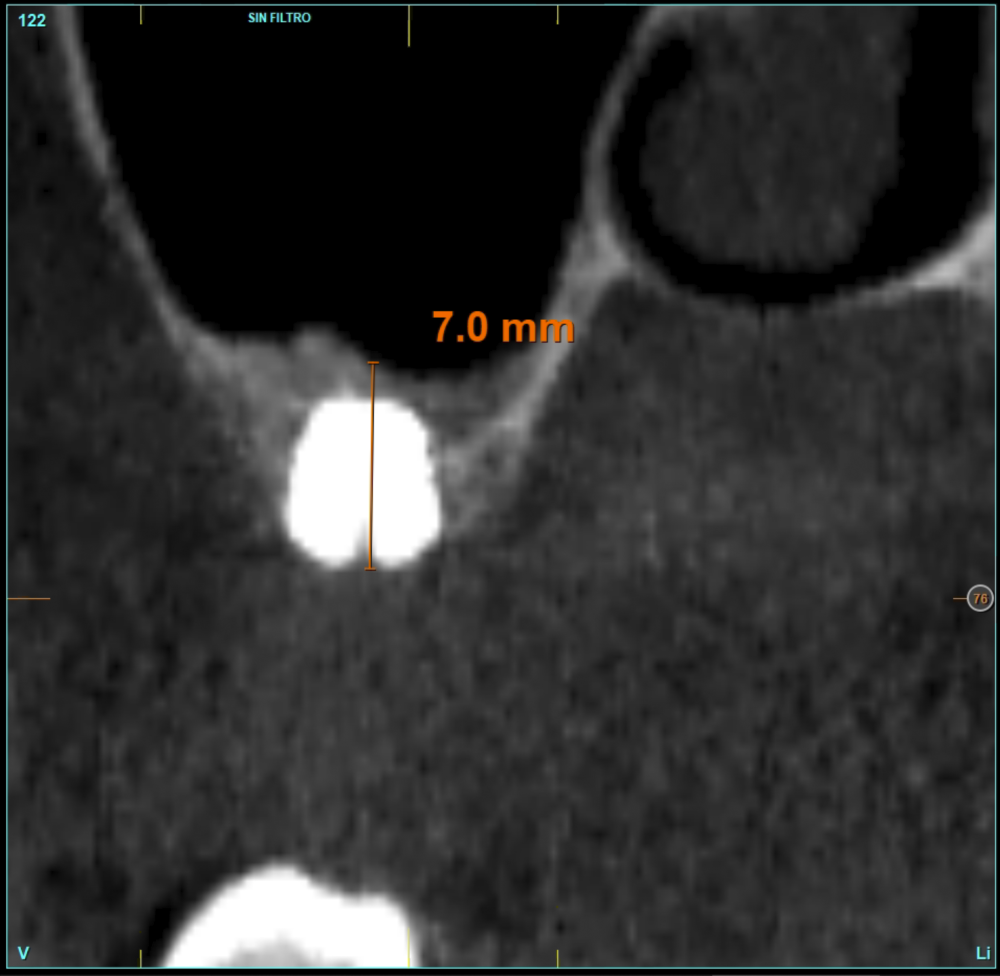

In all cases, a diagnosis was made based on study models, intraoral examination of the patient and performing a Cone-beam analysed using the specific BTI-Scan 3 software (Biotechnology Institute, Vitoria, Alava, Spain).

Patients attend subsequent check-ups performing a control Cone-Beam after 5 months (before loading the implant) and after one year of the load, performing a new measurement in these images to analyse the bone gain and the maintenance of the same. In these check-ups, data are collected on prosthetic complications or crestal bone loss in these patients, as well as possible failures.

The mean height of the residual bone volume was 3.1 mm (+/- 0.3 mm with a range of 3-4 mm). In all cases, transcrestal sinus elevation was performed, with particulate autologous bone obtained from milling the neo alveolus generation zone for implant insertion, being the average of this elevation above the apex of the implant of 2.8 mm (+/- 0.99 range 1.9 -5 mm). In the CT control scan after one year of inserting the studied implants, the bone gain achieved was maintained, no decrease in the volume gained was observed, only three cases showed a decrease of between 0.4 and 0.5 mm of the initial volume at the end (Table).

Figures 2-19 show one of the cases included in the study.